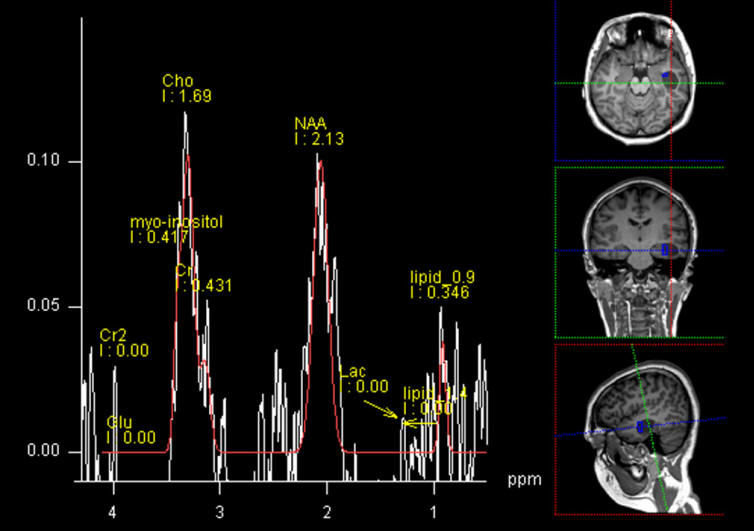

The patient was sent for new investigations and MRI of the brain performed 22-July-2015 showing the mass considerably enlarged in diameter 28.3x18.4 mm anterior to the left inferior horn. Spectroscopy showed high choline levels with glioma nature of the mass.

Choline distribution showing an active nidus medio-basal to the mass.

Spectroscopy of the mass confirming glial nature of the mass.